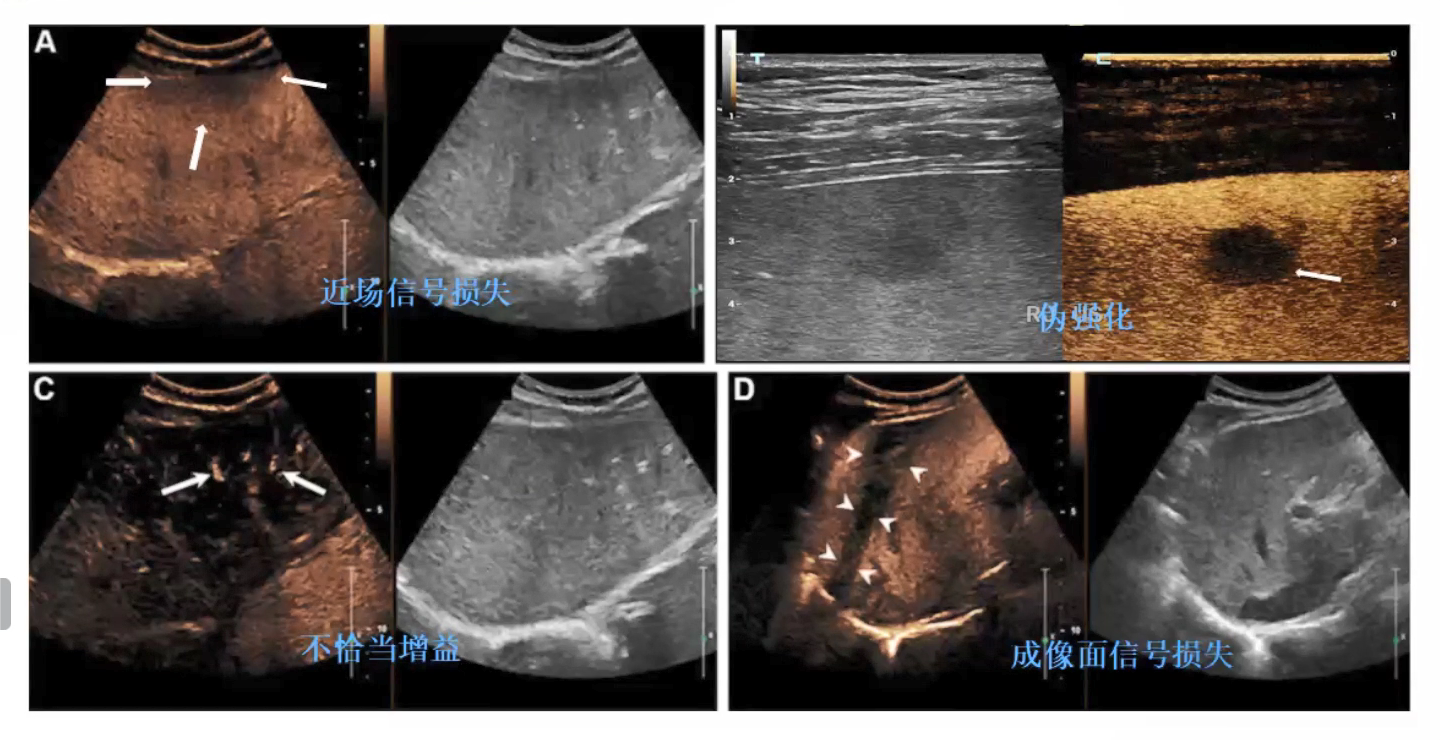

超声造影图像有哪些伪像